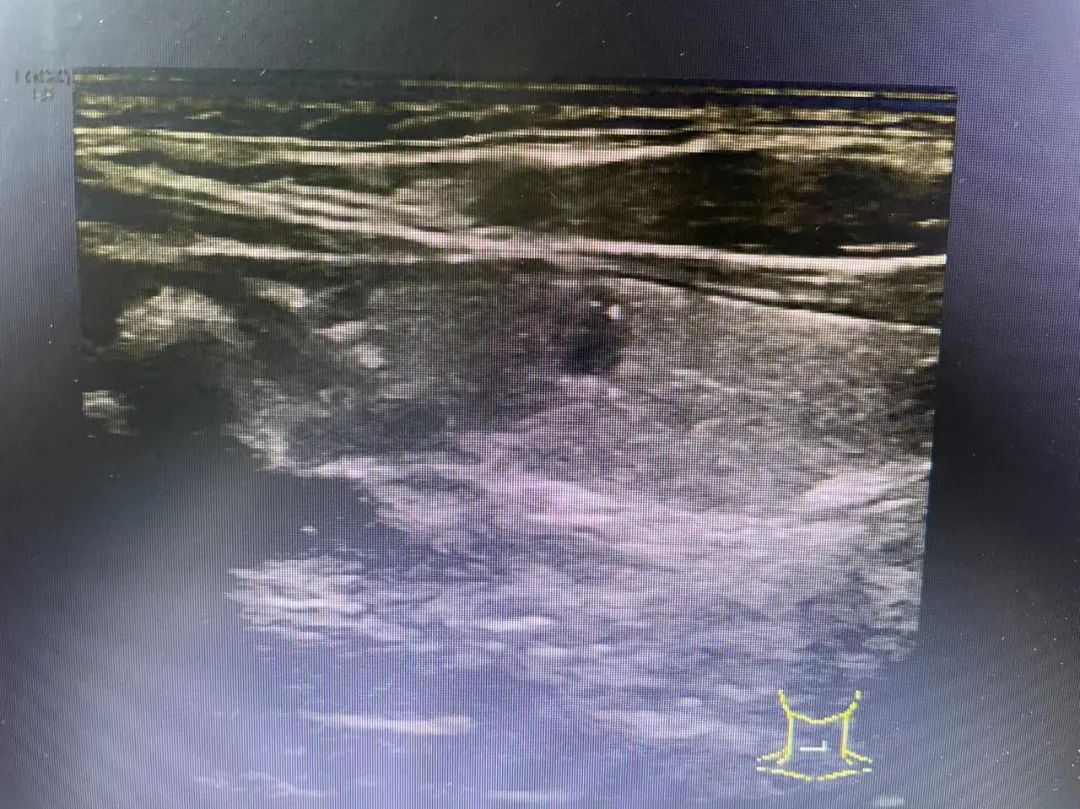

通常结节至少要>1公分以上才能通过临床医生的触诊,可以初步诊断出。随着医学技术的发展,在各种检查手段中,超声机器能更加方便准确地检测出甲状腺结节的大小、形态、位置、血流等情况,更加方便临床医生及患者了解自己结节的情况。

从超声报告中观察,通常甲状腺结节具备几个要素,超声的恶性评分会逐渐增高,从而在结节分级中体现出来。

1、结节内有微钙化;

2、结节与周围甲状腺组织界限不清;

3、纵横比大于1或不规则形的结节;

4、低回声或极低回声;

5、周边及结节內部少量血流信号的“乏血流”改变;